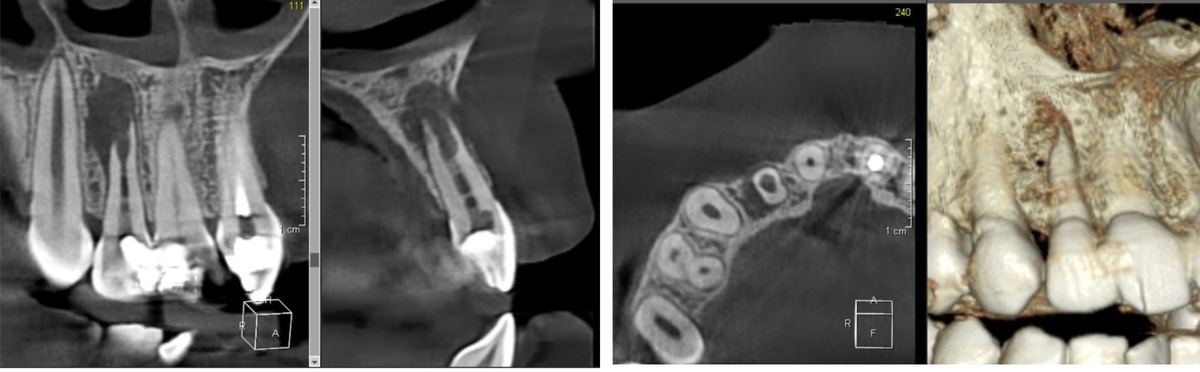

Цервикальная резорбция

Это патологический процесс разрушения тканей зуба в пришеечной области.

На осмотре:

• зуб может выглядеть абсолютно нормально

• иногда - небольшое изменение цвета у десны

Но на КЛКТ:

• видно разрушение тканей

• можно оценить глубину и распространенность процесса

• становится понятно, подлежит ли зуб лечению

Чем это опасно: если не выявить вовремя, разрушение прогрессирует и зуб можно потерять, даже если внешне он долго выглядит здоровым.